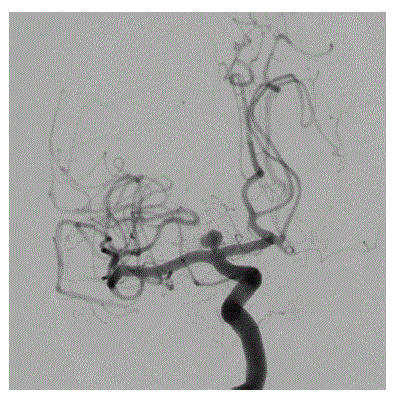

Assinale a alternativa que corresponde à CORRETA topografia do aneurisma cerebral na angiografia abaixo.